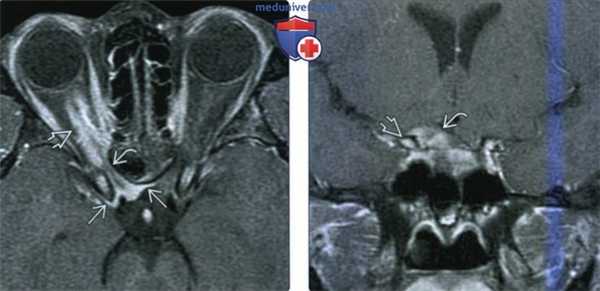

(Слева) МРТ, Т2-ВИ, режим подавления сигнала от жира, аксиальный срез: у женщины 66 лет с выраженным экзофтальмом визуализируется массивное утолщение большого крыла клиновидной кости, окруженное слегка гиперинтенсивным мягкотканным объемным образованием, вовлекающим в процесс глазницу, высокое глубокое жевательное пространство и среднюю черепную ямку.

(Справа) МРТ, STIR, корональный срез: хорошо визуализируется гиперостоз крыла клиновидной кости. Отмечается отчетливый дуральный хвост более гиперинтенсивен мягкотканного компонента объемного образования. (Слева) МРТ, постконтрастное Т1-ВИ, режим подавления сигнала от жира, аксиальный срез: у этой же пациентки определяется интенсивное и равномерное контрастное усиление мягкотканного компонента объемного образования. Гиперостотически измененная кость накапливает контрастное вещество слабоинтенсивно.

(Справа) МРТ, постконтрастное Т1-ВИ, корональный срез: накапливающее контраст мягкотканное образование Визуализируется утолщенное и васкуляризированное крыло клиновидной кости. В смежных отделах прослеживается дуральный хвост. При операции была обнаружена менингиома grade I, а также присутствие опухолевых клеток в резецированной клиновидной кости.